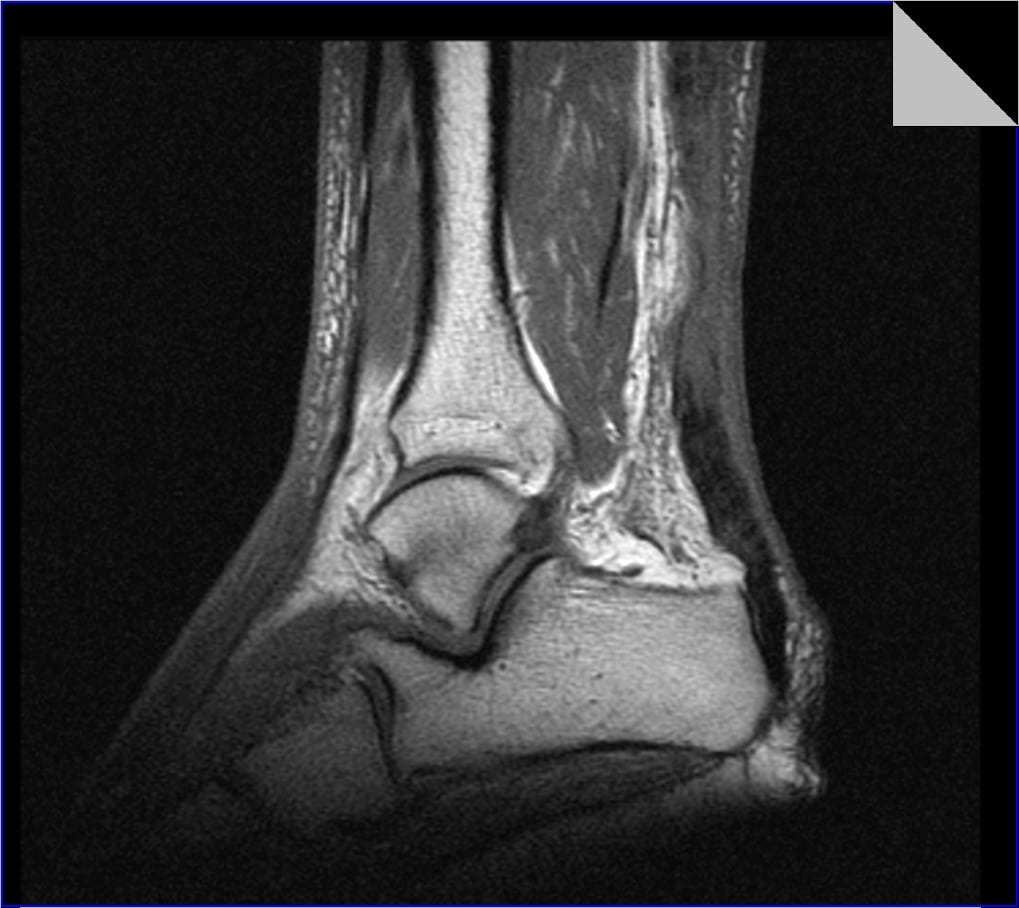

Для диагностирования заболевания требуется проведение ряда инструментальных исследований — МРТ, КТ, рентгенографии, артроскопии. Инфекционный тендовагинит выявляется с помощью биохимических анализов. Лечение — преимущественно консервативное, но при тяжелом течении патологии пациента готовят к хирургическому вмешательству.

Первичный диагноз выставляется на основании осмотра пациента, характера его жалоб, изучения анамнеза. Наличие в нем предшествующих травм, эндокринных расстройств, артрозов, артритов ГС, инфекционных патологий помогает установить не только вид заболевания, но и причину его развития. Для подтверждения диагноза и дифференциации тендовагинита от других патологий проводятся рентгенография, МРТ или КТ.